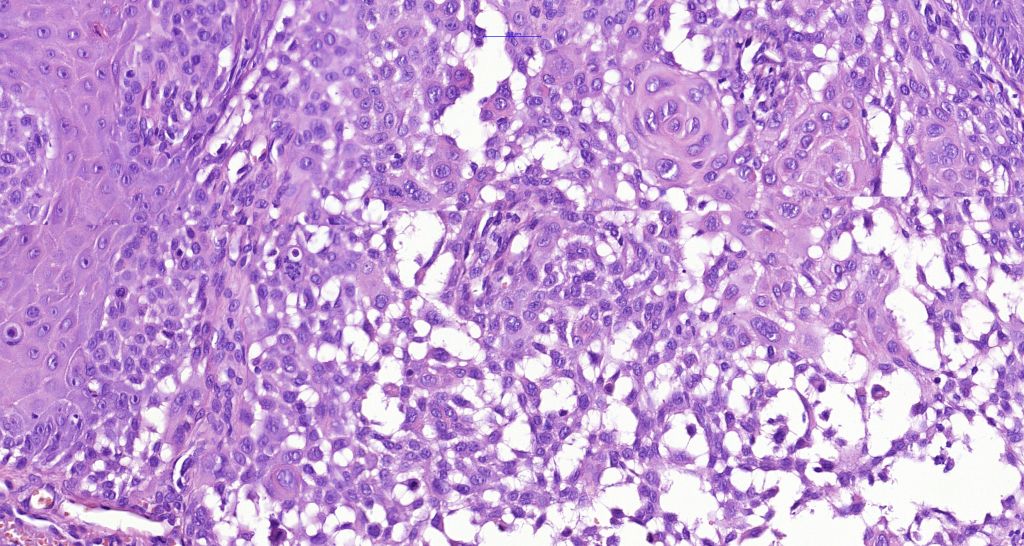

Histological features

•Full thickness dysplasia (carcinoma in situ) involving the epidermis and intraepidermal adnexal elements

•Loss of maturation, nuclear pleomorphism, marked mitotic activity +/- abnormal forms

•Clear cell variant due to glycogen accumulation